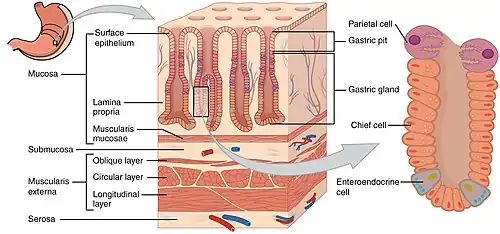

Gastric glands are glands in the lining of the stomach that play an essential role in the process of digestion. Their secretions make up the digestive gastric juice. The gastric glands open into gastric pits in the mucosa. The gastric mucosa is covered in surface mucous cells that produce the mucus necessary to protect the stomach's epithelial lining from gastric acid secreted by parietal cells in the glands, and from pepsin, a secreted digestive enzyme. Surface mucous cells follow the indentations and partly line the gastric pits. Other mucus secreting cells are found in the necks of the glands. These are mucous neck cells that produce a different kind of mucus.

There are two types of gastric gland, the exocrine fundic or oxyntic gland, and the endocrine pyloric gland. The major type of gastric gland is the fundic gland that is present in the fundus and the body of the stomach making up about 80 per cent of the stomach area. These glands are often referred to simply as the gastric glands. The fundic gland contains the parietal cells that produce hydrochloric acid and intrinsic factor, and chief cells that produce pepsinogen and gastric lipase.

The gastric glands are glands in the lining of the stomach that play an essential role in the process of digestion. All of the glands have mucus-secreting foveolar cells (also known as surface mucous cells) that line the stomach and partly line the gastric pits, and mucus-secreting mucous neck cells in the necks of the gastric glands.[1] Mucus lines the entire stomach as gastric mucosa protecting the stomach lining from the effects of gastric acid produced by the parietal cells and released from the fundic glands.

Gastric glands are mostly exocrine glands[2] and are all located beneath the gastric pits within the gastric mucosa.[3] The gastric mucosa is pitted with innumerable gastric pits which each house 3-5 gastric glands.[4] The cells of the exocrine glands (fundic glands) are mucous neck cells, chief cells, and parietal cells.[4] Mucous neck cells produce mucus, parietal cells secrete hydrochloric acid and intrinsic factor, chief cells secrete pepsinogen and gastric lipase.[4]

The fundic glands (or oxyntic glands), are found in the fundus and body of the stomach. They are simple almost straight tubes, two or more of which open into a single duct. Oxyntic means acid-secreting and they secrete hydrochloric acid (HCl) and intrinsic factor.[7]

Types of cell

There are millions of gastric pits (also known as foveolae) in the gastric mucosa and their necessary narrowness determines the tubular form of the gastric gland. More than one tube allows for the accommodation of more than one cell type. The form of each gastric gland is similar; they are all described as having a neck region that is closest to the pit entrance, and basal regions on the lower parts of the tubes.[9] The epithelium from the gastric mucosa travels into the pit and at the neck the epithelial cells change to short columnar granular cells. These cells almost fill the tube and the remaining lumen is continued as a very fine channel.

- Foveolar cells (surface mucous cells) are mucus-producing cells which cover the inside of the stomach, protecting it from the corrosive nature of gastric acid. These cells line the gastric mucosa and follows into the gastric pits.

- Mucous neck cells are located within gastric glands, interspersed between parietal cells. These are shorter than their surface counterpart and contain lesser quantities of mucin granules in their apical surface.

- Chief cells (zymogen cells/peptic cells) – They are found in the basal regions of the gland and release proenzymes or zymogens – pepsinogen (precursor to pepsin), and prorennin (precursor to rennin or chymosin).[10] Prorennin is secreted in young mammals (childhood stage). It is not secreted in adult mammals. Chief cells also produce small amounts of gastric lipase. Gastric lipase contributes little to digestion of fat.

- Parietal cells ("parietal" means "relating to a wall"), also known as oxyntic cells are most numerous on the side walls of the gastric glands. The parietal cells secrete hydrochloric acid (gastric acid). This needs to be readily available for the stomach in a plentiful supply, and so from their positions in the walls, their secretory networks of fine channels called canaliculi can project and ingress into all the regions of the gastric-pit lumen. Another important secretion of the parietal cells is intrinsic factor. Intrinsic factor is a glycoprotein essential for the absorption of vitamin B12.[1] The parietal cells also produce and release bicarbonate ions in response to histamine release from the nearby ECLs, and so serve a crucial role in the pH buffering system.[11]

- Enteroendocrine cells – They are usually present in the basal parts of the gastric glands, which is differentiated into three cell types – enterochromaffin like cells (ECL cells), G cells, and D cells.

Layers of stomach wall

Layers of stomach wall Gastric acid regulation